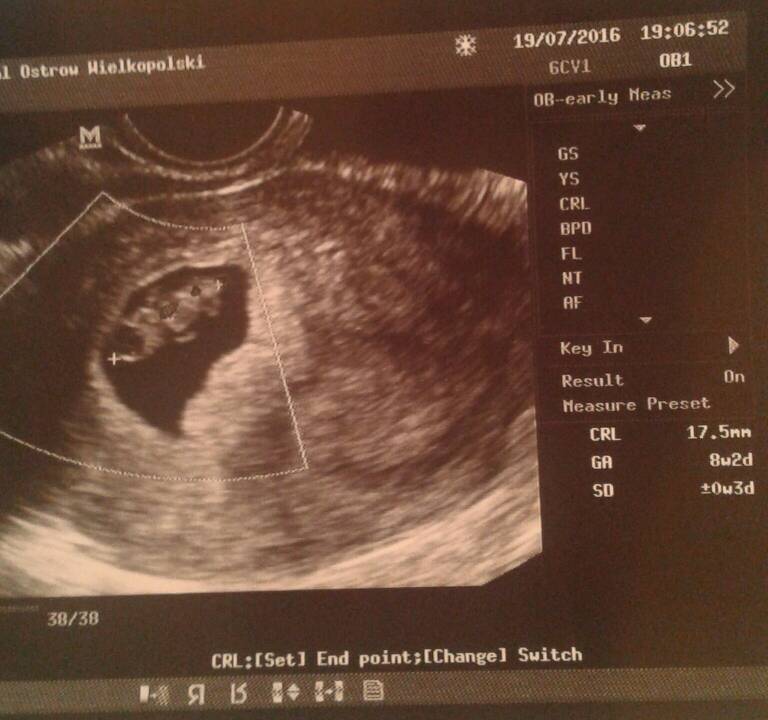

Cluue , witam maluszka :* , mamy z usg taki sam wiek dzieci widzę.